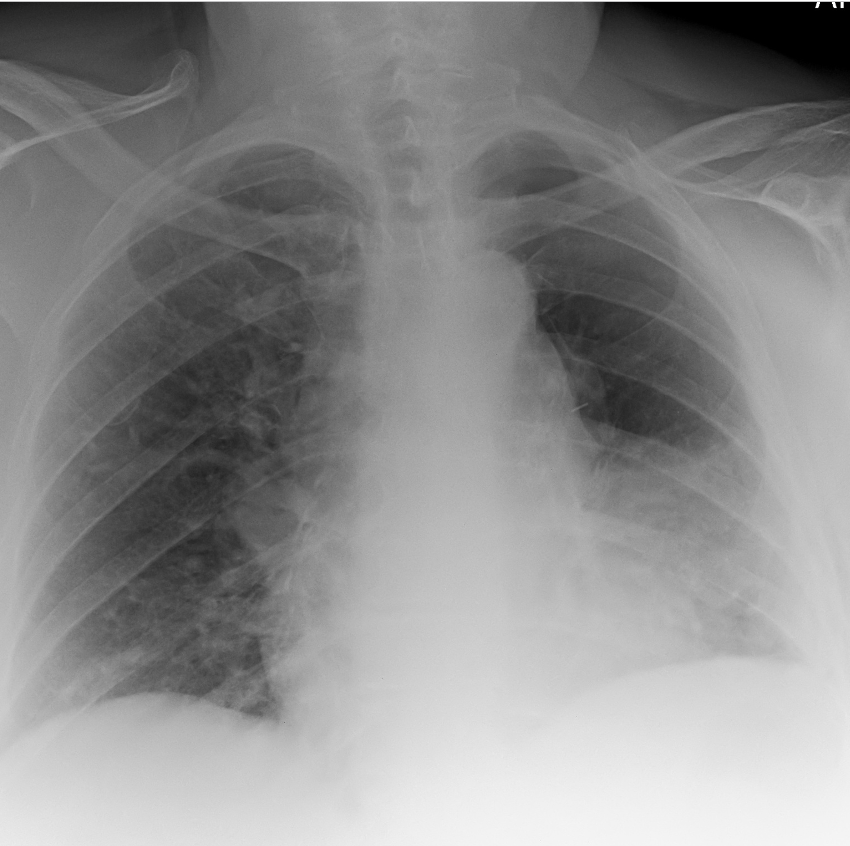

What is this ?

A

Lingular pneumonia

-Infection of the lingula causes the left heart border to become obscured, as shown opposite.